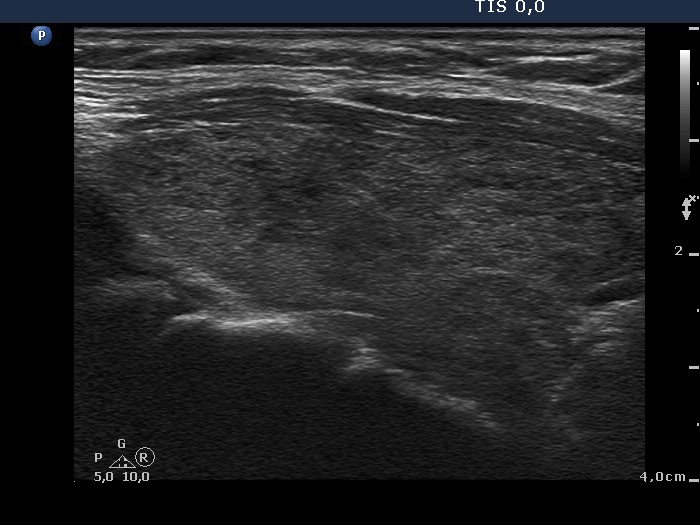

An operated thyroid - Case 1. A patient with an unilateral subtotal thyroidectomy

Three years after surgery (ultrasonographic picture 2)

Upper part of the right lobe, longitudinal scan. There are numerous small hypoechogenic areas in the enlarged thyroid.